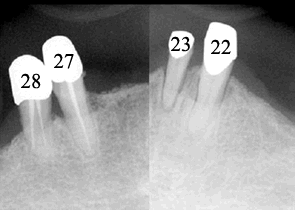

Fig.1

Mr. Fan is 65 years old.  He has had upper and lower overdentures for ten years. Both of them are loose.  He also complains pain associated with upper distal abutments: #8 and 13.  Exam shows generalized advanced chronic periodontits (Fig.1, 2 (upper anterior PAs), 3 (lower anterior PAs).  All of the remaining teeth are nonsalvageable.  The width of the alveolar ridges is adequate (Fig.4 and 7).  The ridge height of the mandible is sufficient, whereas that of the maxilla is questionable (Fig.1).  The patient prefers fixed prosthetics.  We plan to place as many as 24 implants in stages.